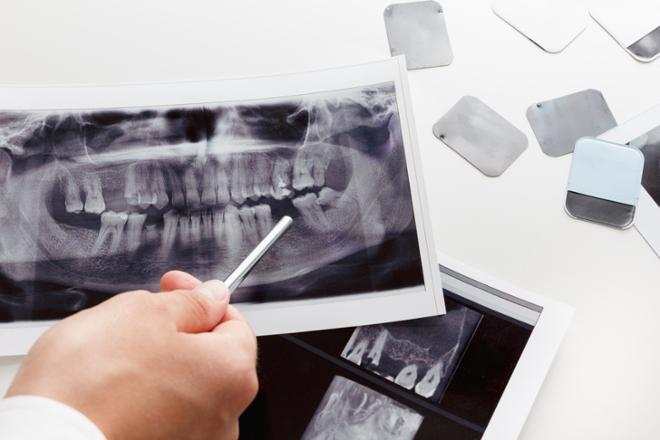

Con las pruebas de un estudio de ortodoncia se establece un plan de tratamiento personalizado para solucionar tus problemas bucodentales.